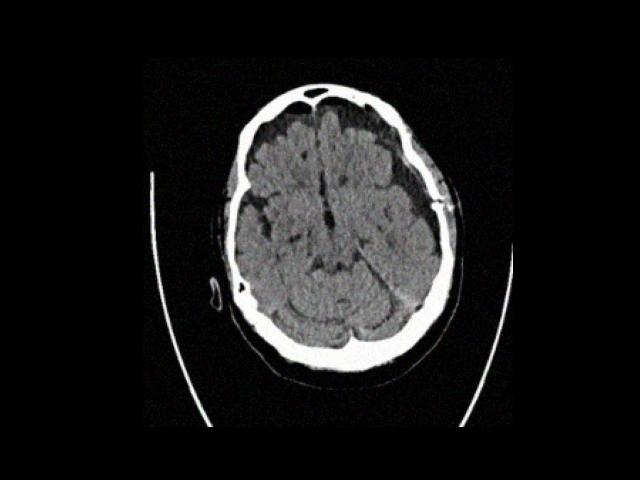

Sample Gallery